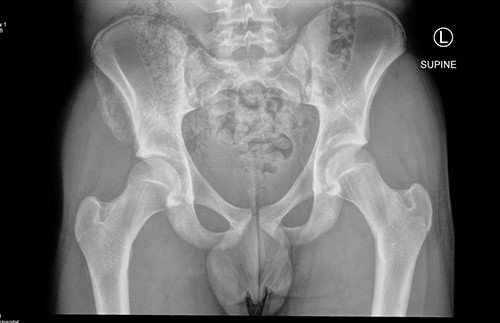

The anterior–posterior plain film X-Ray of pelvis demonstrated an avulsion fracture of the right ASIS and IC apophysis with 1.5 cm displacement (Fig. 1). Lateral view of the hip showed no extension into the joint. There was no radiological evidence of chronic overuse or previous injury. Computed tomography (CT) imaging was performed to better identify the injury; 3D volume reconstruction clearly demonstrated the unique fracture pattern of an ASIS avulsion in addition to an avulsion of the distal iliac apophysis extending ~5 cm with the described displacement (Figs 2–4).

3D reconstruction of tomographic CT scan illustrating avulsion fracture of ASIS and IC apophysis with its latero-inferior displacement (R - Right, L - Left, A - Anterior).